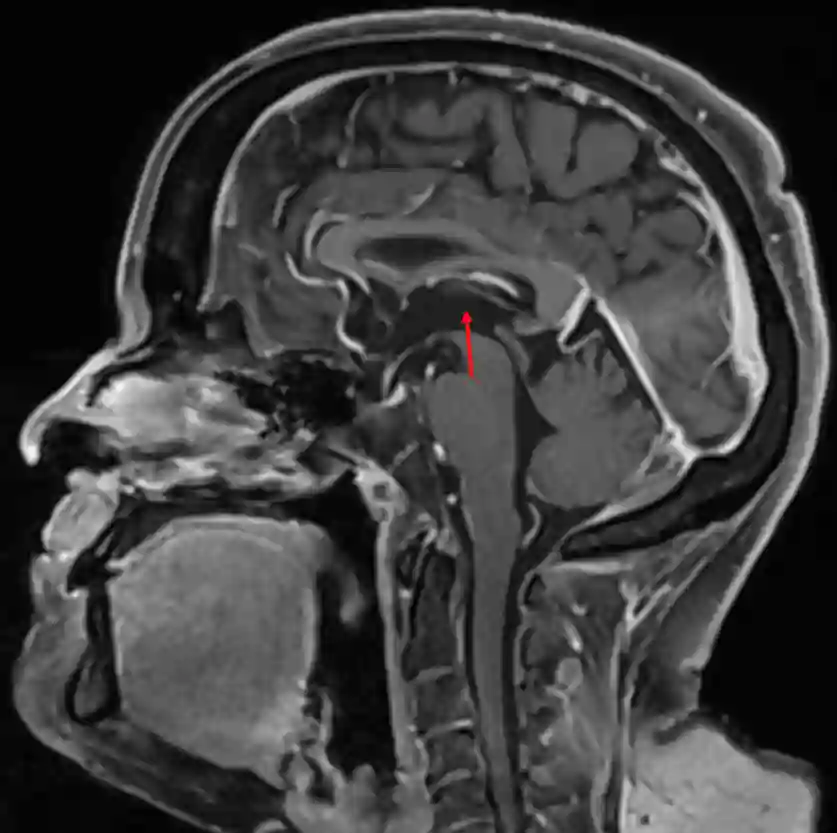

Dritter Ventrikel im MRI

Dritter Ventrikel in der Sagittalebene in einer T1 MRI Sequenz mit Kontrastmittel.